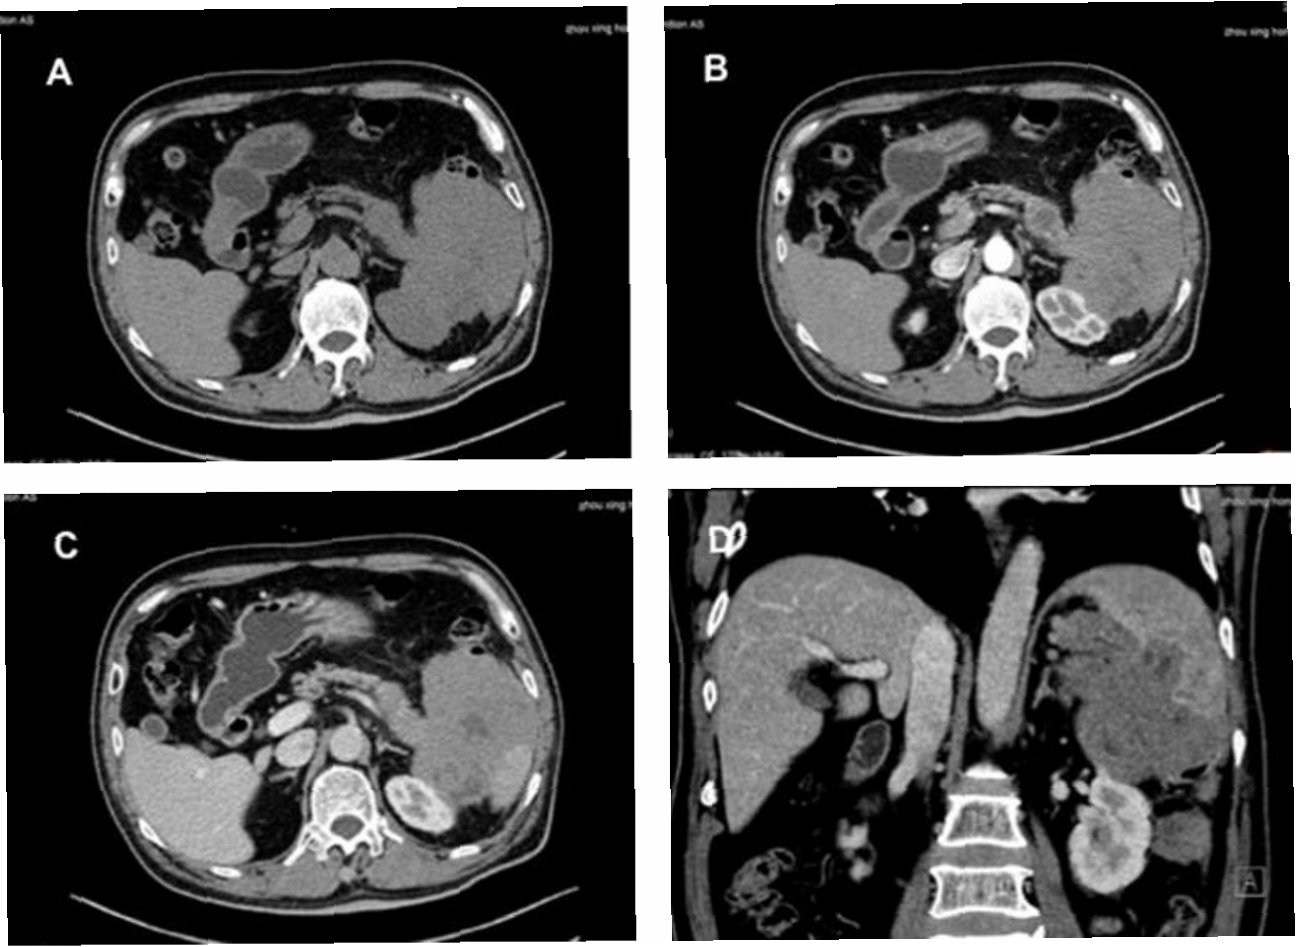

내시경 초음파(EUS, Endoscopic Ultrasound)는 내시경과 초음파 기술을 결합한 최첨단 진단 방법입니다. 일반적인 내시경 검사처럼, EUS는 가느다란 튜브를 식도, 위, 십이지장으로 삽입하여 내부 장기를 직접 관찰합니다. 이 튜브 끝에는 고해상도 초음파 프로브가 장착되어 있어, 내부 장기의 실시간 이미지를 제공합니다. EUS는 림프절을 포함한 주변 조직의 자세한 영상을 얻을 수 있어 림프종 진단에 매우 유용합니다. EUS는 일반적인 초음파 검사보다 더 정확하고, CT나 MRI와 같은 다른 영상 검사보다 더 높은 해상도를 제공하여 작은 병변까지 감지할 수 있습니다.

EUS를 이용한 림프종 진단 과정은 다음과 같습니다. 먼저, 환자는 검사 전에 금식을 해야 합니다. 검사 당일, 환자는 진정제를 투여받아 편안하게 검사를 받을 수 있습니다. 의사는 EUS를 식도, 위, 또는 십이지장으로 삽입하여 림프절을 포함한 주변 조직을 관찰합니다. 초음파 영상으로 림프절의 크기, 모양, 내부 구조 등을 평가하여 림프종의 의심 여부를 판단합니다. 필요에 따라, EUS 유도하 세침 생검(EUS-FNA)을 시행하여 림프절 조직을 채취합니다. 채취된 조직은 병리과에서 분석하여 림프종의 종류를 확진합니다. 검사 후, 환자는 회복실에서 휴식을 취한 후 귀가할 수 있으며, 검사 결과는 추후 외래 진료를 통해 확인합니다.

EUS-FNA(Endoscopic Ultrasound-guided Fine Needle Aspiration)는 EUS를 이용하여 림프절이나 종양에서 세포 또는 조직을 채취하는 시술입니다EUS를 통해 실시간으로 림프절을 보면서, 가느다란 바늘을 사용하여 정확하게 조직을 채취할 수 있습니다. EUS-FNA는 림프종의 종류를 정확하게 진단하고, 치료 계획을 수립하는 데 매우 중요한 역할을 합니다. 채취된 조직은 세포 병리 검사, 면역 조직 화학 검사, 유전자 검사 등을 통해 림프종의 종류와 특성을 파악합니다. EUS-FNA는 림프종 진단의 정확성을 높이고, 불필요한 수술을 줄이는 데 기여합니다.